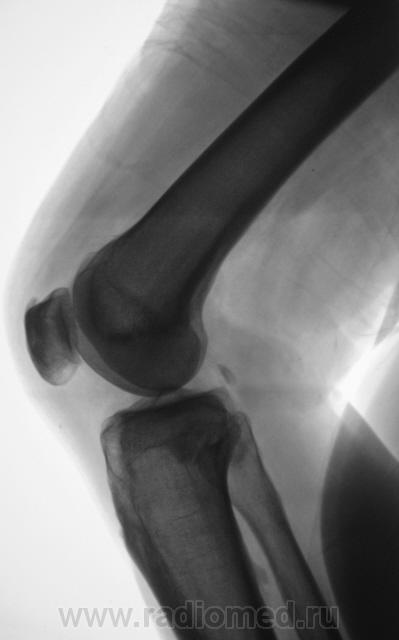

Мужчина средних лет, крепкий, ведущий активный образ жизни, занимающийся дозировано «элементами спорта», полковник милиции, в последнее время (несколько лет) почувствовал боли в области правого коленного сустава.

Снимки ниже.

Просьба высказать мнения по представленным иллюстрациям.

Энтезопатия надколенника, перегрузочная болезнь б/б кости(подозрение на неполный перелом).

Очень похожая картина на консолидированный перелом б\б кости. В проекции м\б кости определяется периостальная реакция или патологическая перестройка костной ткани.

Есть  признаки  артроза  и  синовита . Была  повреждена  передняя  крестообразная  связка.

Боли почти постоянные, усиливаются после физической нагрузки.

Валентин Львович, я бы направил пациента на ультразвук коленного сустава для детально "рассмотрения" суставной поверхности надколенника. Был у меня подобный случай - очень схож и анамнез и характер жалоб.  Его (больного) бы ещё положить и руками "подавить"... но это уже удел травматологов.